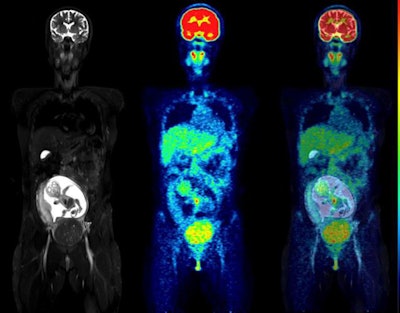

Coronal slices of MRI (left), PET (center), and fused PET/MRI (right) of a woman at 18 weeks of pregnancy. Of particular interest is the level of uptake in the fetal organs. While the heart showed high F-18 FDG uptake, the brain had only a low level of glucose consumption, especially compared with brain uptake of the mother. This pattern of low glucose consumption has previously been noted even in mature fetuses. All images courtesy of the Journal of Nuclear Medicine.Cervical and ovarian cancers are the most common gynecological cancers diagnosed during pregnancy, and malignancy during pregnancy is increasing, according to the authors. Studies show the most common type of malignancy is uterine cervical cancer.

All fetuses were visible in detail on the MRI scans, which allowed the delineation of their body contours. F-18 FDG activity was unevenly distributed in the fetal body. The hearts were generally visible, while the brain showed low uptake, the results showed.